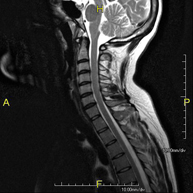

- RM Columna cervical

Prueba diagnóstica no invasiva que consiste en la obtención de imágenes de alta definición anatómica de la columna cervical mediante el empleo de un campo electromagnético y ondas de radio (con un emisor y un receptor). No utiliza radiación ionizante. Indicaciones: traumatismo, degeneración de la columna, hernias. - RM Columna dorsal